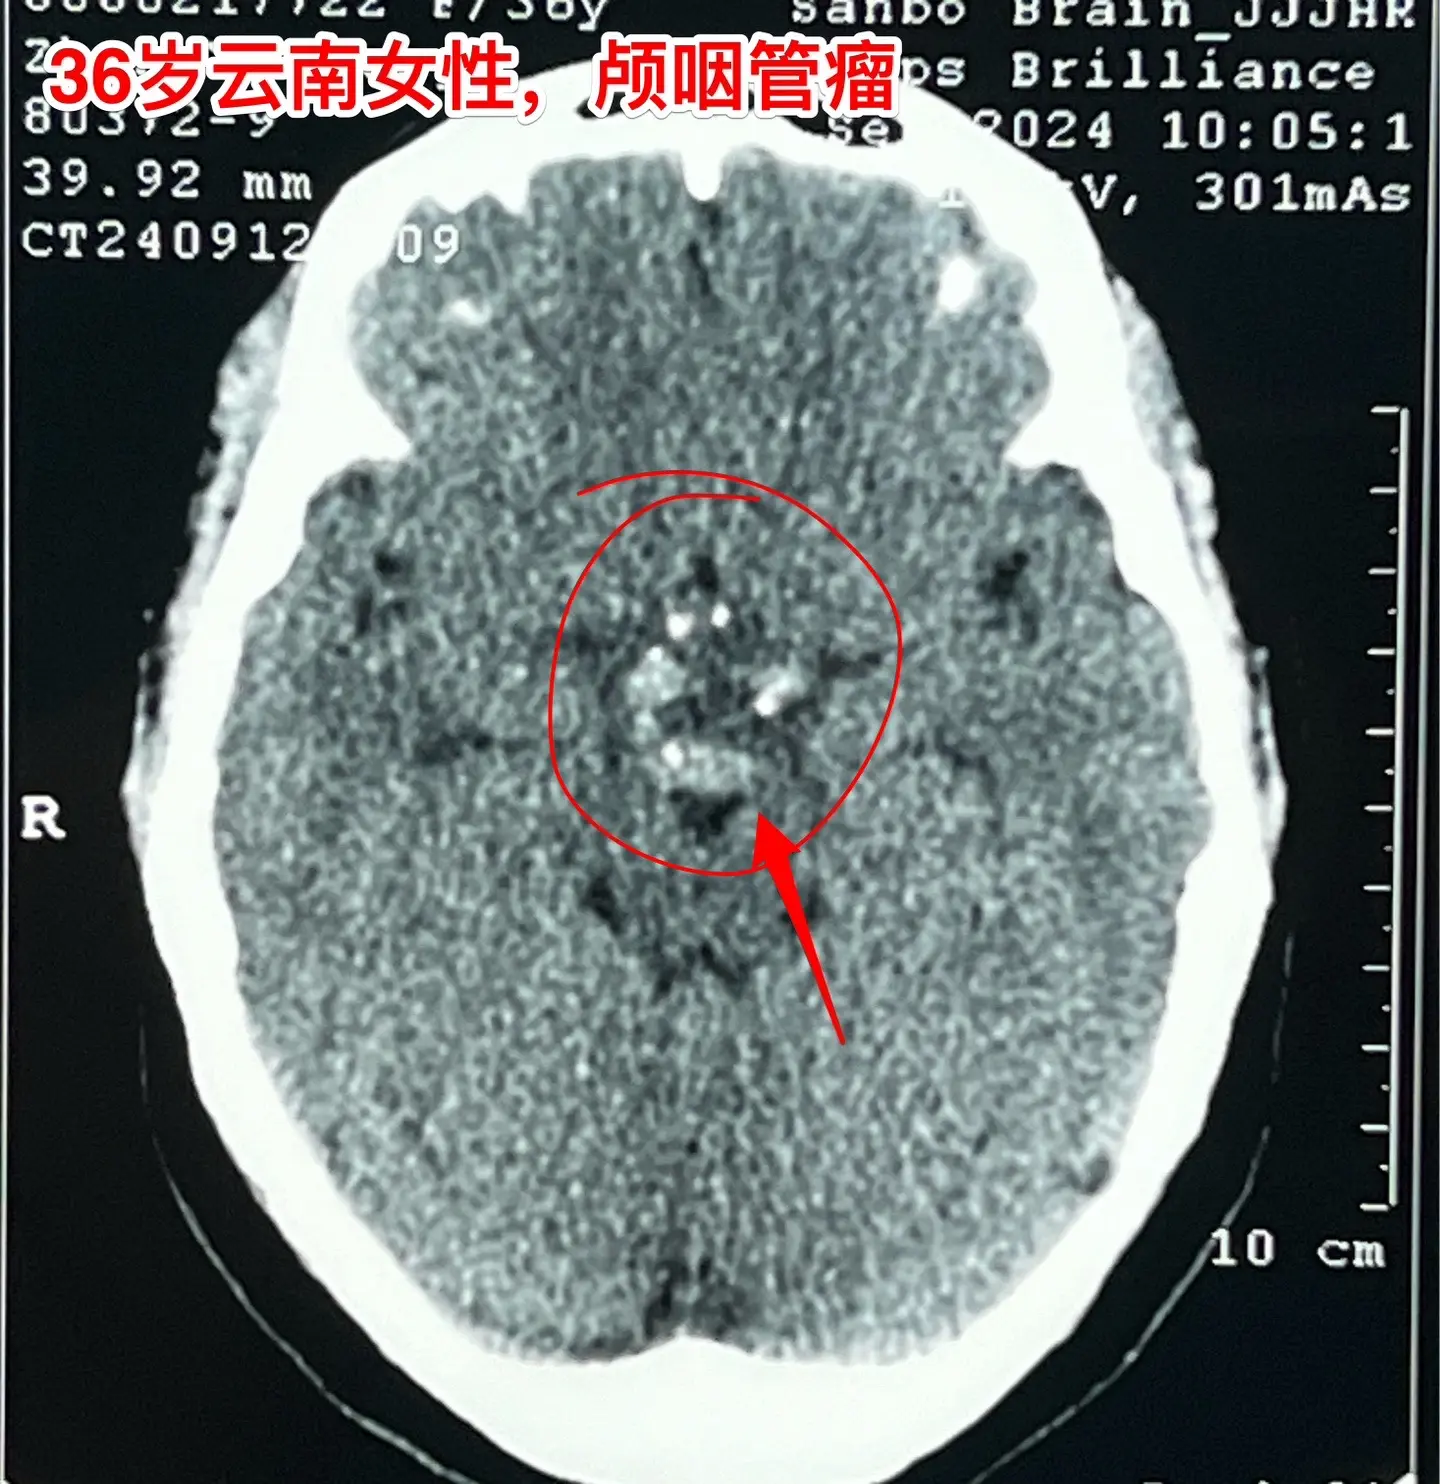

36岁玉溪市女性,颅咽管瘤手术后视力改善。一开始出现内分泌紊乱,随后出现头痛、视力下降。发现颅咽管瘤后于9月11日到我科住院,因为发烧,等到9月24日才作了手术。 好饭不怕晚!手术很顺利,肿瘤得到完全切除,垂体柄保留了30%。手术后病人的身体恢复很快,视力也好转了。